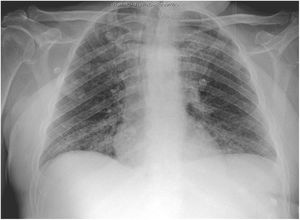

El segundo caso se trata de un varón de 59 años con factores de riesgo vasculares y trastorno por abuso de sustancias. Ingresó a los 3 días de presentar fiebre elevada, tos y malestar general. En la analítica presentaba leucocitosis (20400/mm3) con neutrofilia (87%), linfopenia (900/mm3), elevación de dímero-D (1500ng/ml), creatinina (2,8mg/dl), sodio (157mmol/l), LDH (761UI/l), CPK (780UI/l), transaminasas, PCR (180mg/l) y ferritina (2900ng/ml) así como hipoxemia con hipocapnia. La radiografía de tórax mostraba un infiltrado intersticial bibasal (fig. 2). Se realizó un estudio microbiológico similar al primer caso, obteniendo positiva la PCR para SARS-CoV-2.